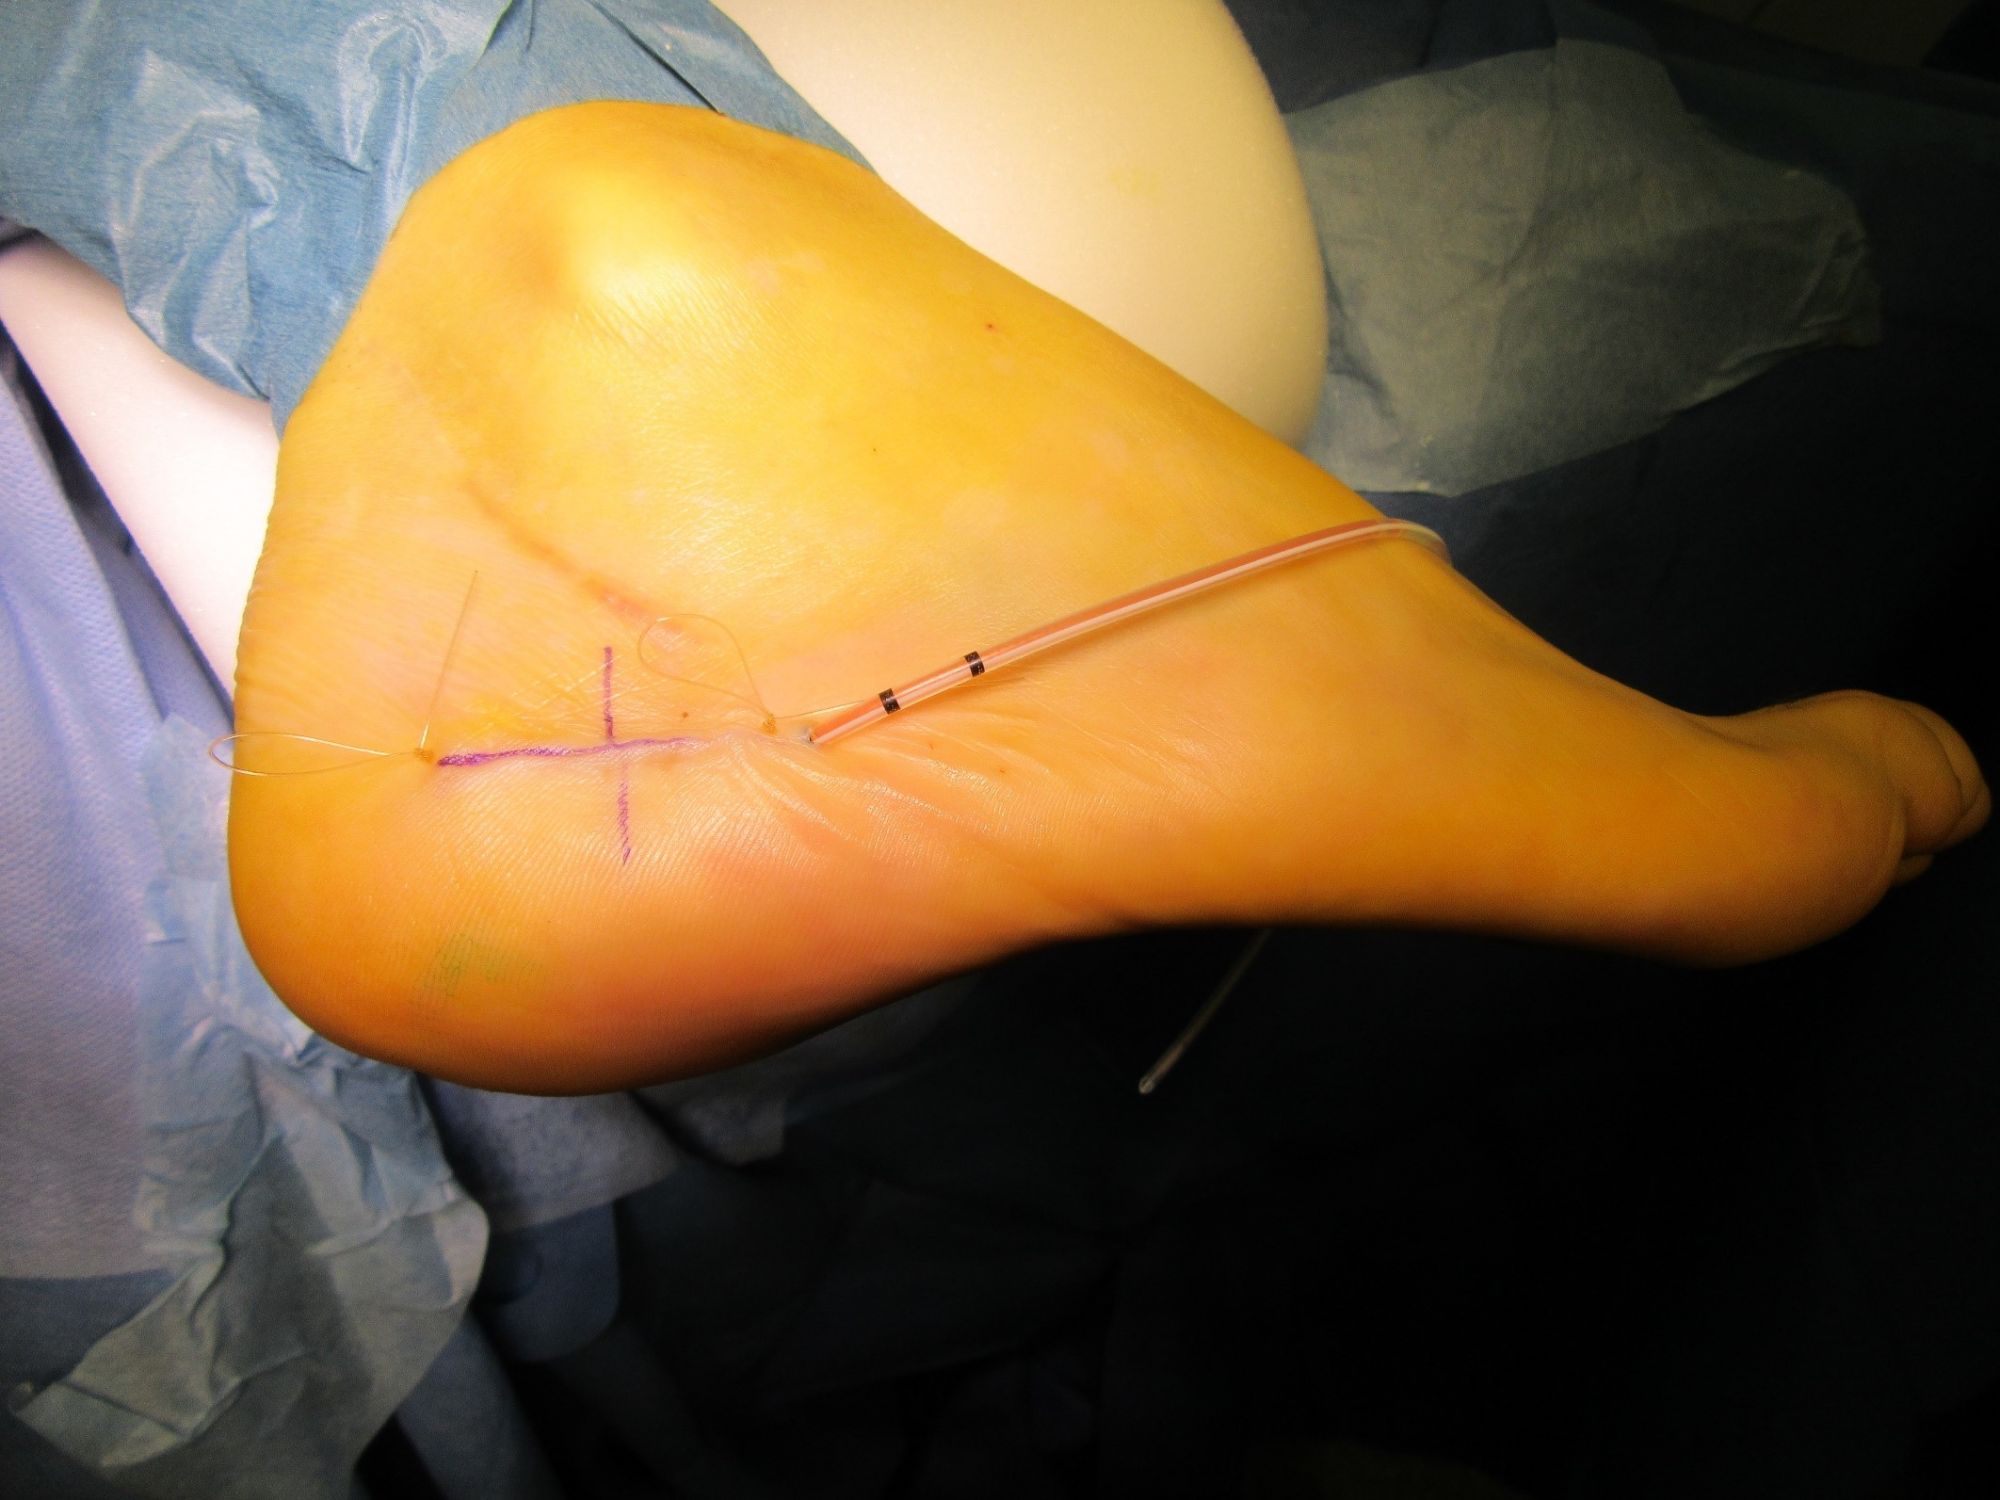

Abbildung 4: OP-Situs

Darstellung der Ausrissverletzung, Refixation durch Anker.

Zum Lesen der Bildbeschreibung und zur Vollansicht bitte das Bild anklicken. Bild: Manfred Thomas.